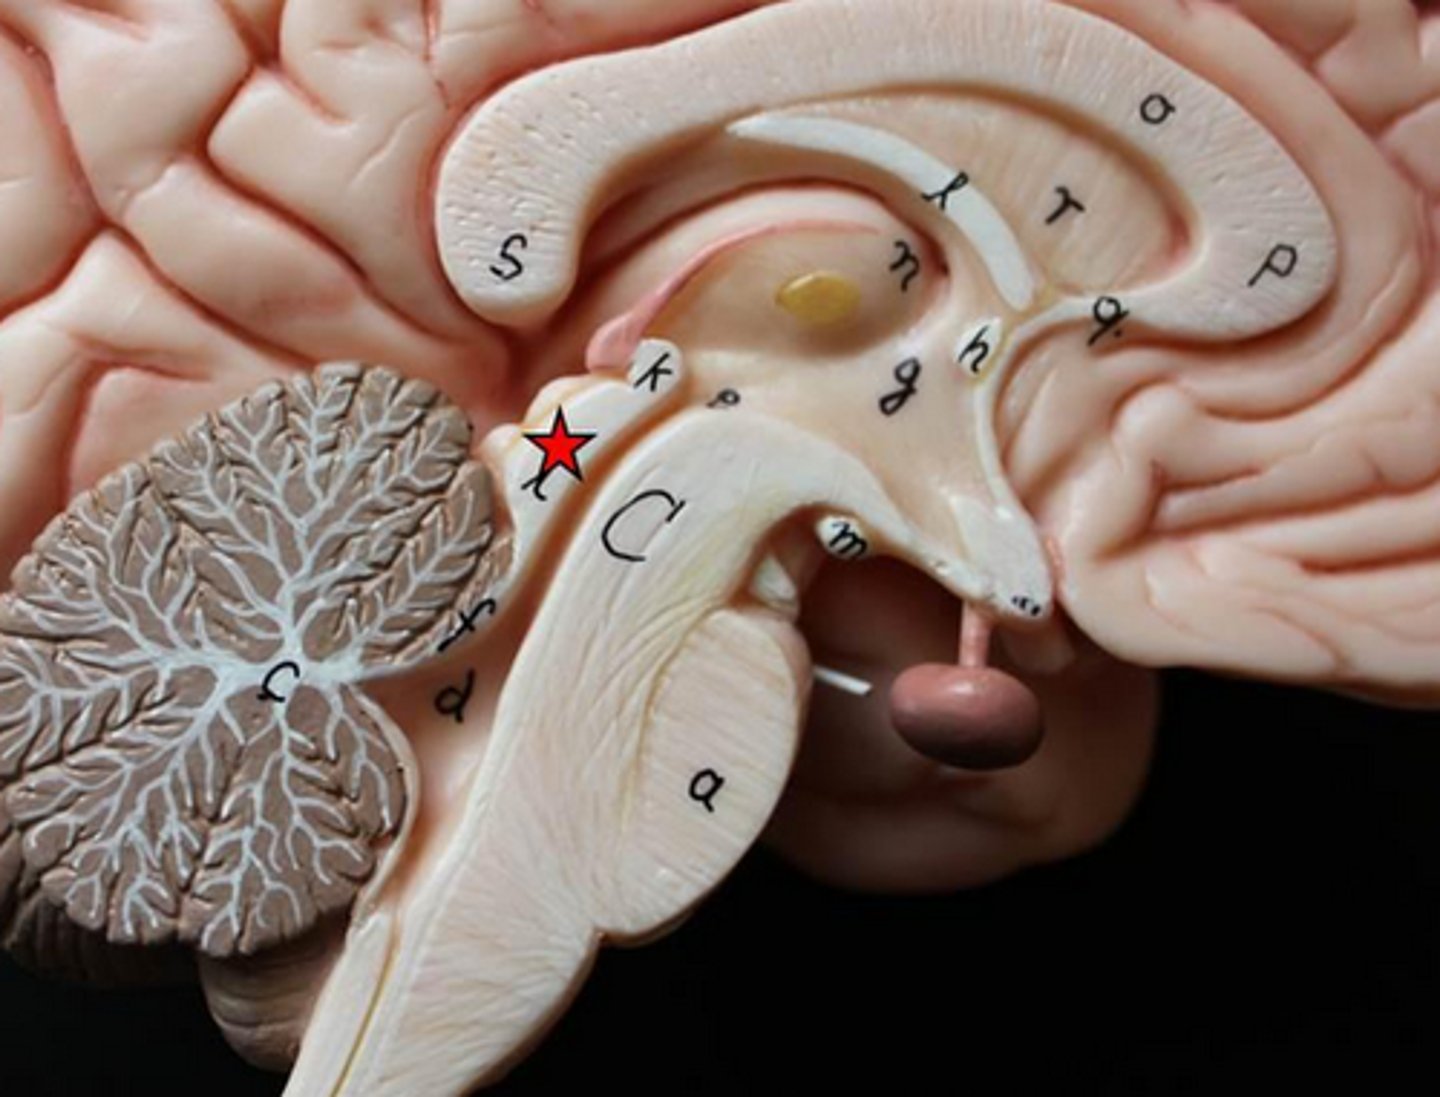

ventricles of the brain

canals in the brain that contain cerebrospinal fluid

lateral ventricles

Ventricles located in each cerebral hemisphere

third ventricle

the ventricle located in the center of the diencephalon

fourth ventricle

between pons and cerebellum

interventricular foramen

opening that connects the lateral ventricles and 3rd ventricle

cerebral aqueduct

connects the third and fourth ventricles

cerebral spinal fluid

made by choroid plexus

CSF function

buoyancy (supports 95% of the weight of the brain), protection (liquid cushion for brain tissue), chemical stability (transports nutrients to brain and waste away from brain)

Hydrocephalus

accumulation of CSF in the spaces of the brain